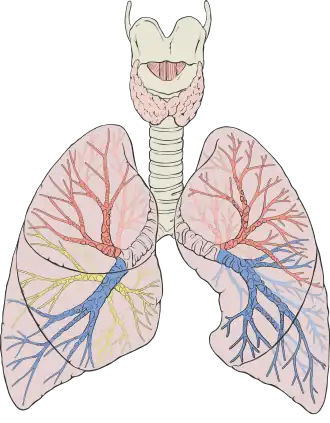

![]() Diagram of the human lungs with the respiratory tract visible, and different colours for each lobe | |

Humans have two lungs, a right lung and a left lung. They are situated within the thoracic cavity of the chest. The right lung is bigger than the left, and the left lung shares space in the chest with the heart. The lungs together weigh approximately 1.3 kilograms (2.9 lb), and the right is heavier. The lungs are part of the lower respiratory tract that begins at the trachea and branches into the bronchi and bronchioles, which receive air breathed in via the conducting zone. These divide until air reaches microscopic alveoli, where gas exchange takes place. Together, the lungs contain approximately 2,400 kilometers (1,500 mi) of airways and 300 to 500 million alveoli. Each lung is enclosed within a pleural sac of two pleurae which allows the inner and outer walls to slide over each other whilst breathing takes place, without much friction. The inner visceral pleura divides each lung as fissures into sections called lobes. The right lung has three lobes and the left has two. The lobes are further divided into bronchopulmonary segments and lobules. The lungs have a unique blood supply, receiving deoxygenated blood sent from the heart to receive oxygen (the pulmonary circulation) and a separate supply of oxygenated blood (the bronchial circulation).

In humans, the lungs are located in the chest on either side of the heart in the rib cage. They are conical in shape with a narrow rounded apex at the top, and a broad concave base that rests on the convex surface of the diaphragm.[1] The apex of the lung extends into the root of the neck, reaching shortly above the level of the sternal end of the first rib. The lungs stretch from close to the backbone in the rib cage to the front of the chest and downwards from the lower part of the trachea to the diaphragm.[1]

The left lung shares space with the heart, and has an indentation in its border called the cardiac notch of the left lung to accommodate this.[2][3] The front and outer sides of the lungs face the ribs, which make light indentations on their surfaces. The medial surfaces of the lungs face towards the centre of the chest, and lie against the heart, great vessels, and the carina where the trachea divides into the two main bronchi.[3] The cardiac impression is an indentation formed on the surfaces of the lungs where they rest against the heart.

Each lung is divided into sections called lobes by the infoldings of the visceral pleura as fissures. Lobes are divided into segments, and segments have further divisions as lobules. There are three lobes in the right lung and two lobes in the left lung.